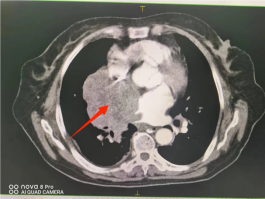

(三)肺鳞癌

行IMRT治疗一疗程(35次)后,经CT检查所示,肿瘤明显缩小。